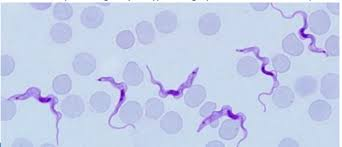

trypanosoma brucei gambiense trypomastigota

trypanosoma brucei gambiense trypomastigota